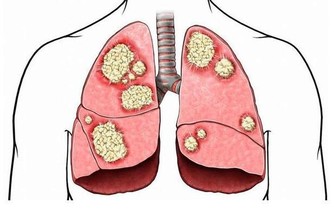

蔡世澤說,高油、高鈉是增加心血管疾病重要因素,過多油脂會造成血管堵塞,

超標的鈉則會導致血壓飆高以及血管彈性疲乏、硬化,增加心血管疾病發生,